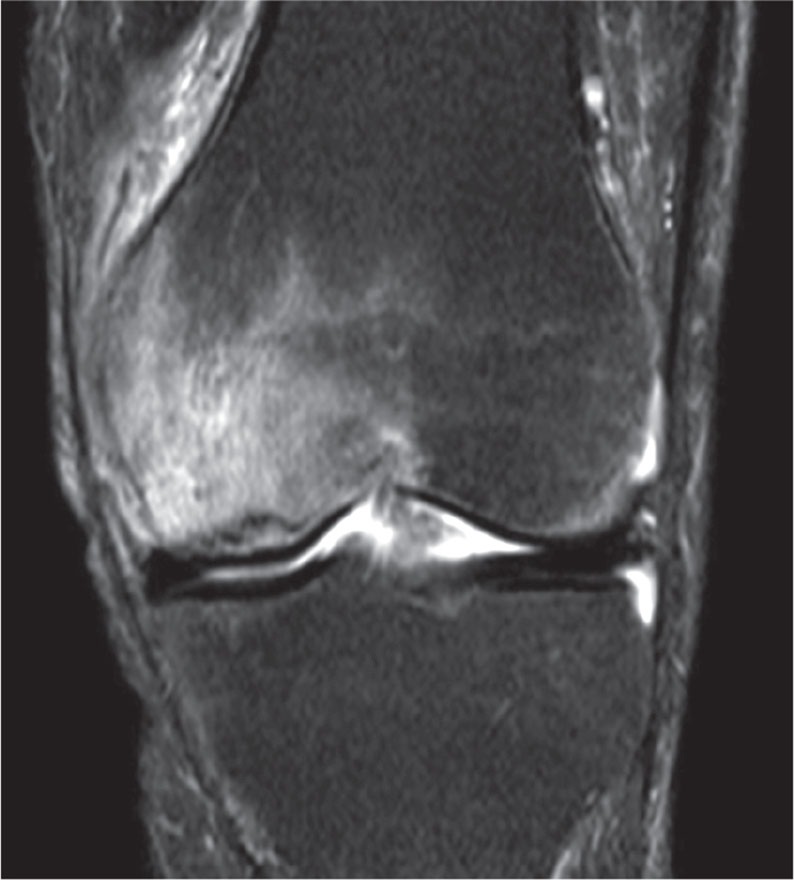

Figure 2.

MR image showing bone marrow edema of the medial femur condyle with a focal subchondral lesion typical of osteonecrosis.

The start of symptoms of SPONK is classically acute onset of pain without predisposing trauma and the most common finding on physical examination is localized tenderness over the medial femoral condyle (Lotke et al. 1982). The initial radiograph may be negative, especially if the symptoms are of short duration, and the diagnosis is therefore often missed at this stage. Later on, radiographs typically show a subchondral radiolucent lesion in the weight-bearing area of the medial or lateral femoral condyle (Figure 1). In some patients, the radiographs may remain normal during the whole course of the disease (Lotke et al. 1977, Houpt et al. 1983) and changes are only seen with bone scintigraphy or magnetic resonance imaging (Koshino 1982). Scintigraphy, performed within a few days of the onset of pain, shows a high uptake in the affected femoral condyle (Rozing et al. 1980). MRI shows bone marrow edema in the affected condyle. This and a focal subchondral lesion (Figure 2) are considered the cardinal signs for diagnosis of osteonecrosis (Björkengren et al. 1990, Yates et al. 2007).